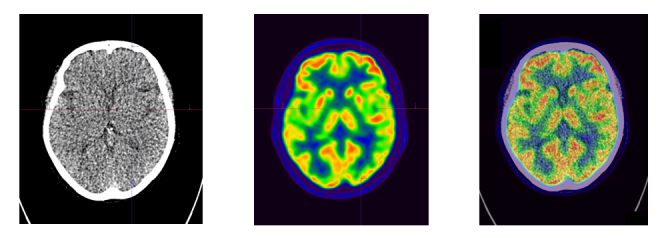

FDG-PET is a nuclear medicine procedure that can used to show images of sugar metabolism. .

Exemplary case studies on FDG-PET/CT diagnostics:

Case study of dementia: